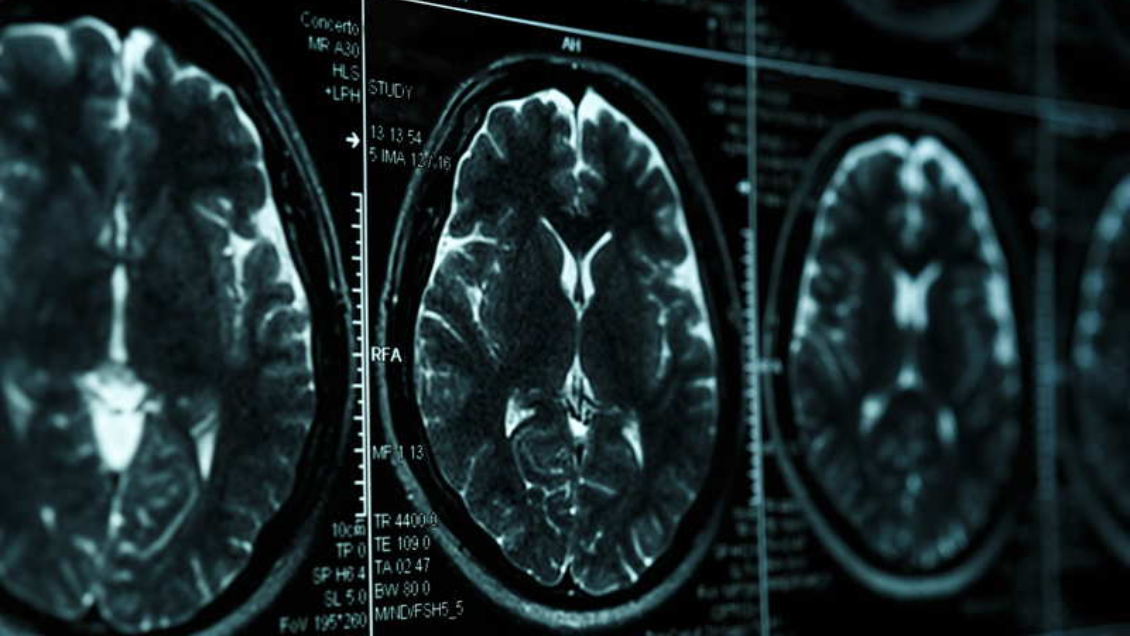

Expertos chinos informan del primer caso de un paciente de 19 años con Alzhéimer

El joven presentó problemas de memoria desde los 17 años y un año más tarde presentó de pérdida significativa de memoria reciente.

La situación se agravó hasta el punto de que no podía recordar si se había alimentado y por el deterioro de sus funciones tuvo que abandonar la escuela.

Jia Jianping, que lideró el estudio, afirmó que no no tenía un historial familiar ni problemas genéticos o enfermedades causantes. Pidió más atención a la posibilidad de que el Alzhéimer se presente en jóvenes.